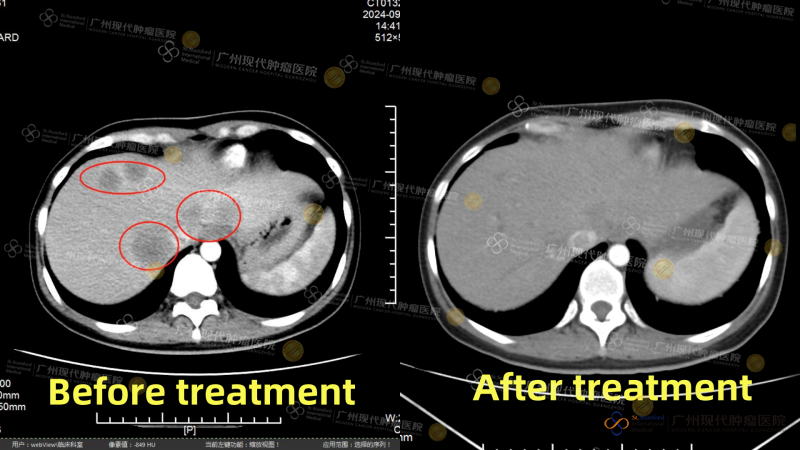

Ny. Zhang dari Malaysia (metastasis hati pasca operasi kanker kolon sigmoid) pada Juli 2024, menjalani operasi pengangkatan tumor di RS setempat. Namun, dalam waktu singkat setelah operasi, kondisinya memburuk dengan cepat, muncul metastasis difus di hati, dengan ukuran tumor terbesar sekitar 46×41mm. Karena tumor melibatkan area pembuluh darah penting, pengendalian lokal menjadi sangat sulit dan pengobatan konvensional menghadapi banyak keterbatasan. Pada September 2024, ia datang ke Modern Cancer Hospital Guangzhou dan menerima cryoablation serta terapi intervensi. Tiga bulan setelah pengobatan, hasil pemeriksaan ulang menunjukkan tumor di area yang diterapi mengecil secara signifikan, dan kondisi mental pasien membaik secara nyata. Pemeriksaan lanjutan pada Februari 2025 menunjukkan bahwa tumor hampir sepenuhnya menghilang, kondisi fisik pulih dengan baik, dan pasien sudah dapat makan sendiri serta menjalani aktivitas harian secara mandiri.

Gambar perbandingan CT sebelum dan sesudah pengobatan Ny. Zhang